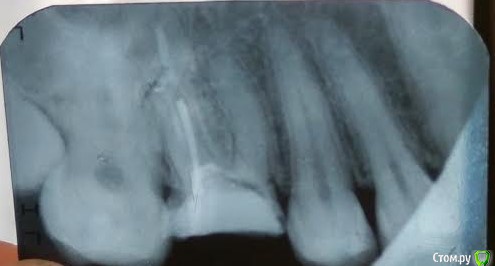

AlenaBeg Опубликовано 12 января, 2017 Поделиться Опубликовано 12 января, 2017 Добрый день.Во время беременности перелечивала зуб верхнюю 6ку (вроде 26 по номеру), коронковая часть была значительно разрушена (не было большей половины одной стенки), врач поставил в канал штифт и нарастил коронковую часть зуба. Снимки после лечения не делали по понятной причине. Через 5 лет часть маленькая часть пломбы откололась, я пошла ставить коронку на зуб к другому врачу (первый врач, у которого был удачно пролечен не один зуб переехал). Врач сказал, что каналы запломбированы не до конца, вскрыл зуб, перепломбировал 2 канала, отметил, что третий канал непроходим и нужно проводить депофорез. Во время чистки каналов сильно кровило, врач сказал, что немного травмировал десну. Предстояло 3 процедуры депофореза с интервалом в 2 недели между ними. После первой процедуры было чувство распирания в зубе и периодическая боль в течение пары дней. После второй распирание и боль усилились, длились около недели. К третей процедуре боли не было, но было болезненно прикасаться к зубу со стороны щеки, ближе к соседнему зубу (5). Было ощущение, что маленький кусочек зуба будто шатается. Очень испугалась, решив, что сломался корень зуба. Рассказав это лечащему врачу, он отправил меня на снимок, сказал, что действительно скололась небольшая часть зуба и перед постановкой вкладки и коронки мне ее просто уберут, с корнем все в порядке. С третьей пломбой я ходила около 4х недель, т.к. врач был на больничном. После снятия временной пломбы оказалось, что сильно воспалена десна, врач сказал, что это реакция на длительное хождение со временной пломбой, и все заживет в течение полу года. В этот же день я была направленна в ортопедическое отделение. Врач, взглянув на снимок, сказала, что зуб под удаление, почему не сказала, только что как минимум есть непроходимый канал. Удивлению не было предела. После разговора с лечащим врачом и заведующей терапевтического отделения меня перенаправили к другому ортопеду. Пришлось снова ходить с временной пломбой дней пять. Вот тут началась ужастная боль со всей стороны наружней стенки зуба (со стороны щеки), невозможно было ничем прикоснуться к ней, сразу появлялась резкая боль, напоминающая боль при гематоме. На приеме ортопеда (по плану была установка вкладки) я обо всем оповестила врача. Он снял пломбу, но болевые ощущения при касании этой стенки зуба были очень сильны. Врач сказал, что от временной пломбы произошло расширение зуба, и нужно немного дать отдохнуть зубу. Врач спилил коронковую часть зуба, поставил фотопломбу и назначил прием через 10 дней. Над самим зубом рядом с соседним (5) нависала ярко красная десна, которая болела, если ее заденешь (посмотреть это мне удалось при помощи стоматологического зеркала). Зуб со стороны щеки также болел, если постучать по нему. Боль странная, сразу проходит, если зуб не трогать, но при постукивании будто чувствуются шевеления зуба. К дате приема я заболела, прием пришлось перенести. Десна, нависающая над зубом, перестала болеть, стала не такой красно, но не исчезла. При постукивании осталась чувствительность в маленьком кусочку зуба рядом с 5кой, не такая ярко выраженная, как раньше. Пока дождусь приема лечащего врача, с ума сойду. Не покидают меня мысли, что с зубом что-то не так.Вопросы:1. Есть снимки зуба до, во время и после лечения. На последних мне мерещится трещина в корне, где был проведен депофорез. Очень прошу посмотреть. Возможно, нет смысла пытаться ставить вкладку и коронку.2. Как десна (или это даже не десна) оказалась на коронковой части зуба? Куда она денется потом? Спасибо! По поводу снимков. Я уже поняла, что фотографировала неправильно. Проблемный зуб с левой стороны. Но так как первых двух снимков (до лечения и перед депофорезом) на руках нет, потерялись у врача, хорошо, что успела сделать фотографии, последние 2 сфотографировала также. Они есть у меня. Ссылка на комментарий

AlenaBeg Опубликовано 12 января, 2017 Автор Поделиться Опубликовано 12 января, 2017 На прием ко врачу обязательно пойду после полного выздоровления. А по снимкам совсем ничего не видно? На последнем на корне, где непроходимый канал, как будто трещина. Ссылка на комментарий

red_butler Опубликовано 12 января, 2017 Поделиться Опубликовано 12 января, 2017 А по снимкам совсем ничего не видно? по снимкам зуб требует повторного лечения корневых каналов, депофорез таковым не является. Но главное это объем сохраненных твердых тканей, если его недостаточно, или есть трещина то зуб удалять Ссылка на комментарий